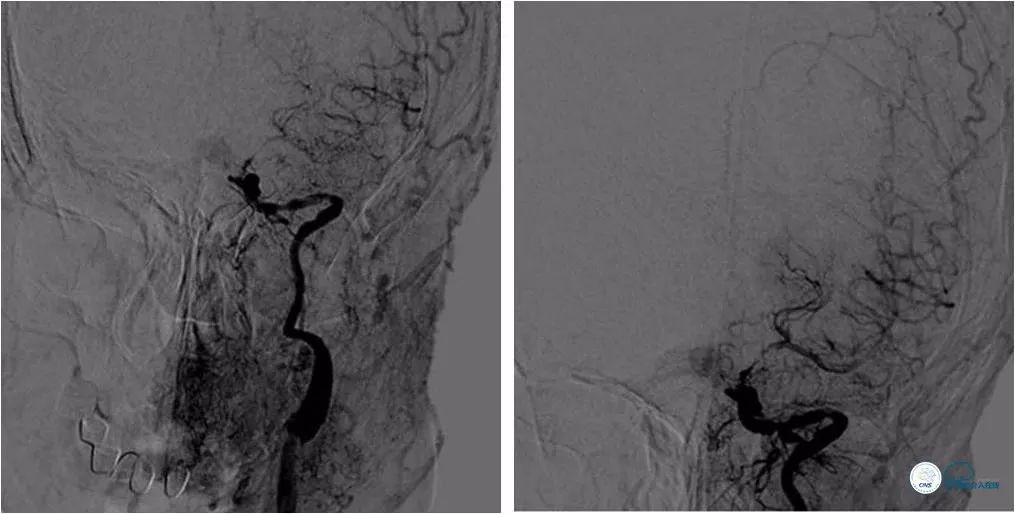

DSA:左颈内动脉C6-7段重度狭窄,狭窄程度重,病变较长,前向血流减慢(图4,5),后循环造影显示后循环向前循环侧支代偿不足(图6)。

图6